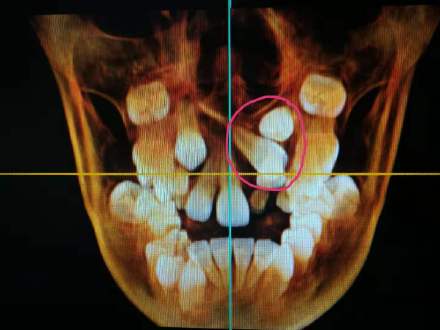

孩子8歲,三顆埋伏牙無法正常萌出

埋伏牙就是害羞不露麵,長期存在於(yu) 牙槽骨裏的牙齒。一般來說,需要拍片才能看清它的真實麵貌。所以不少**從(cong) 來不知道自己有埋伏牙的情況。不過有的埋伏牙可以牽引,但是有的無法牽引的可能需要拔牙。